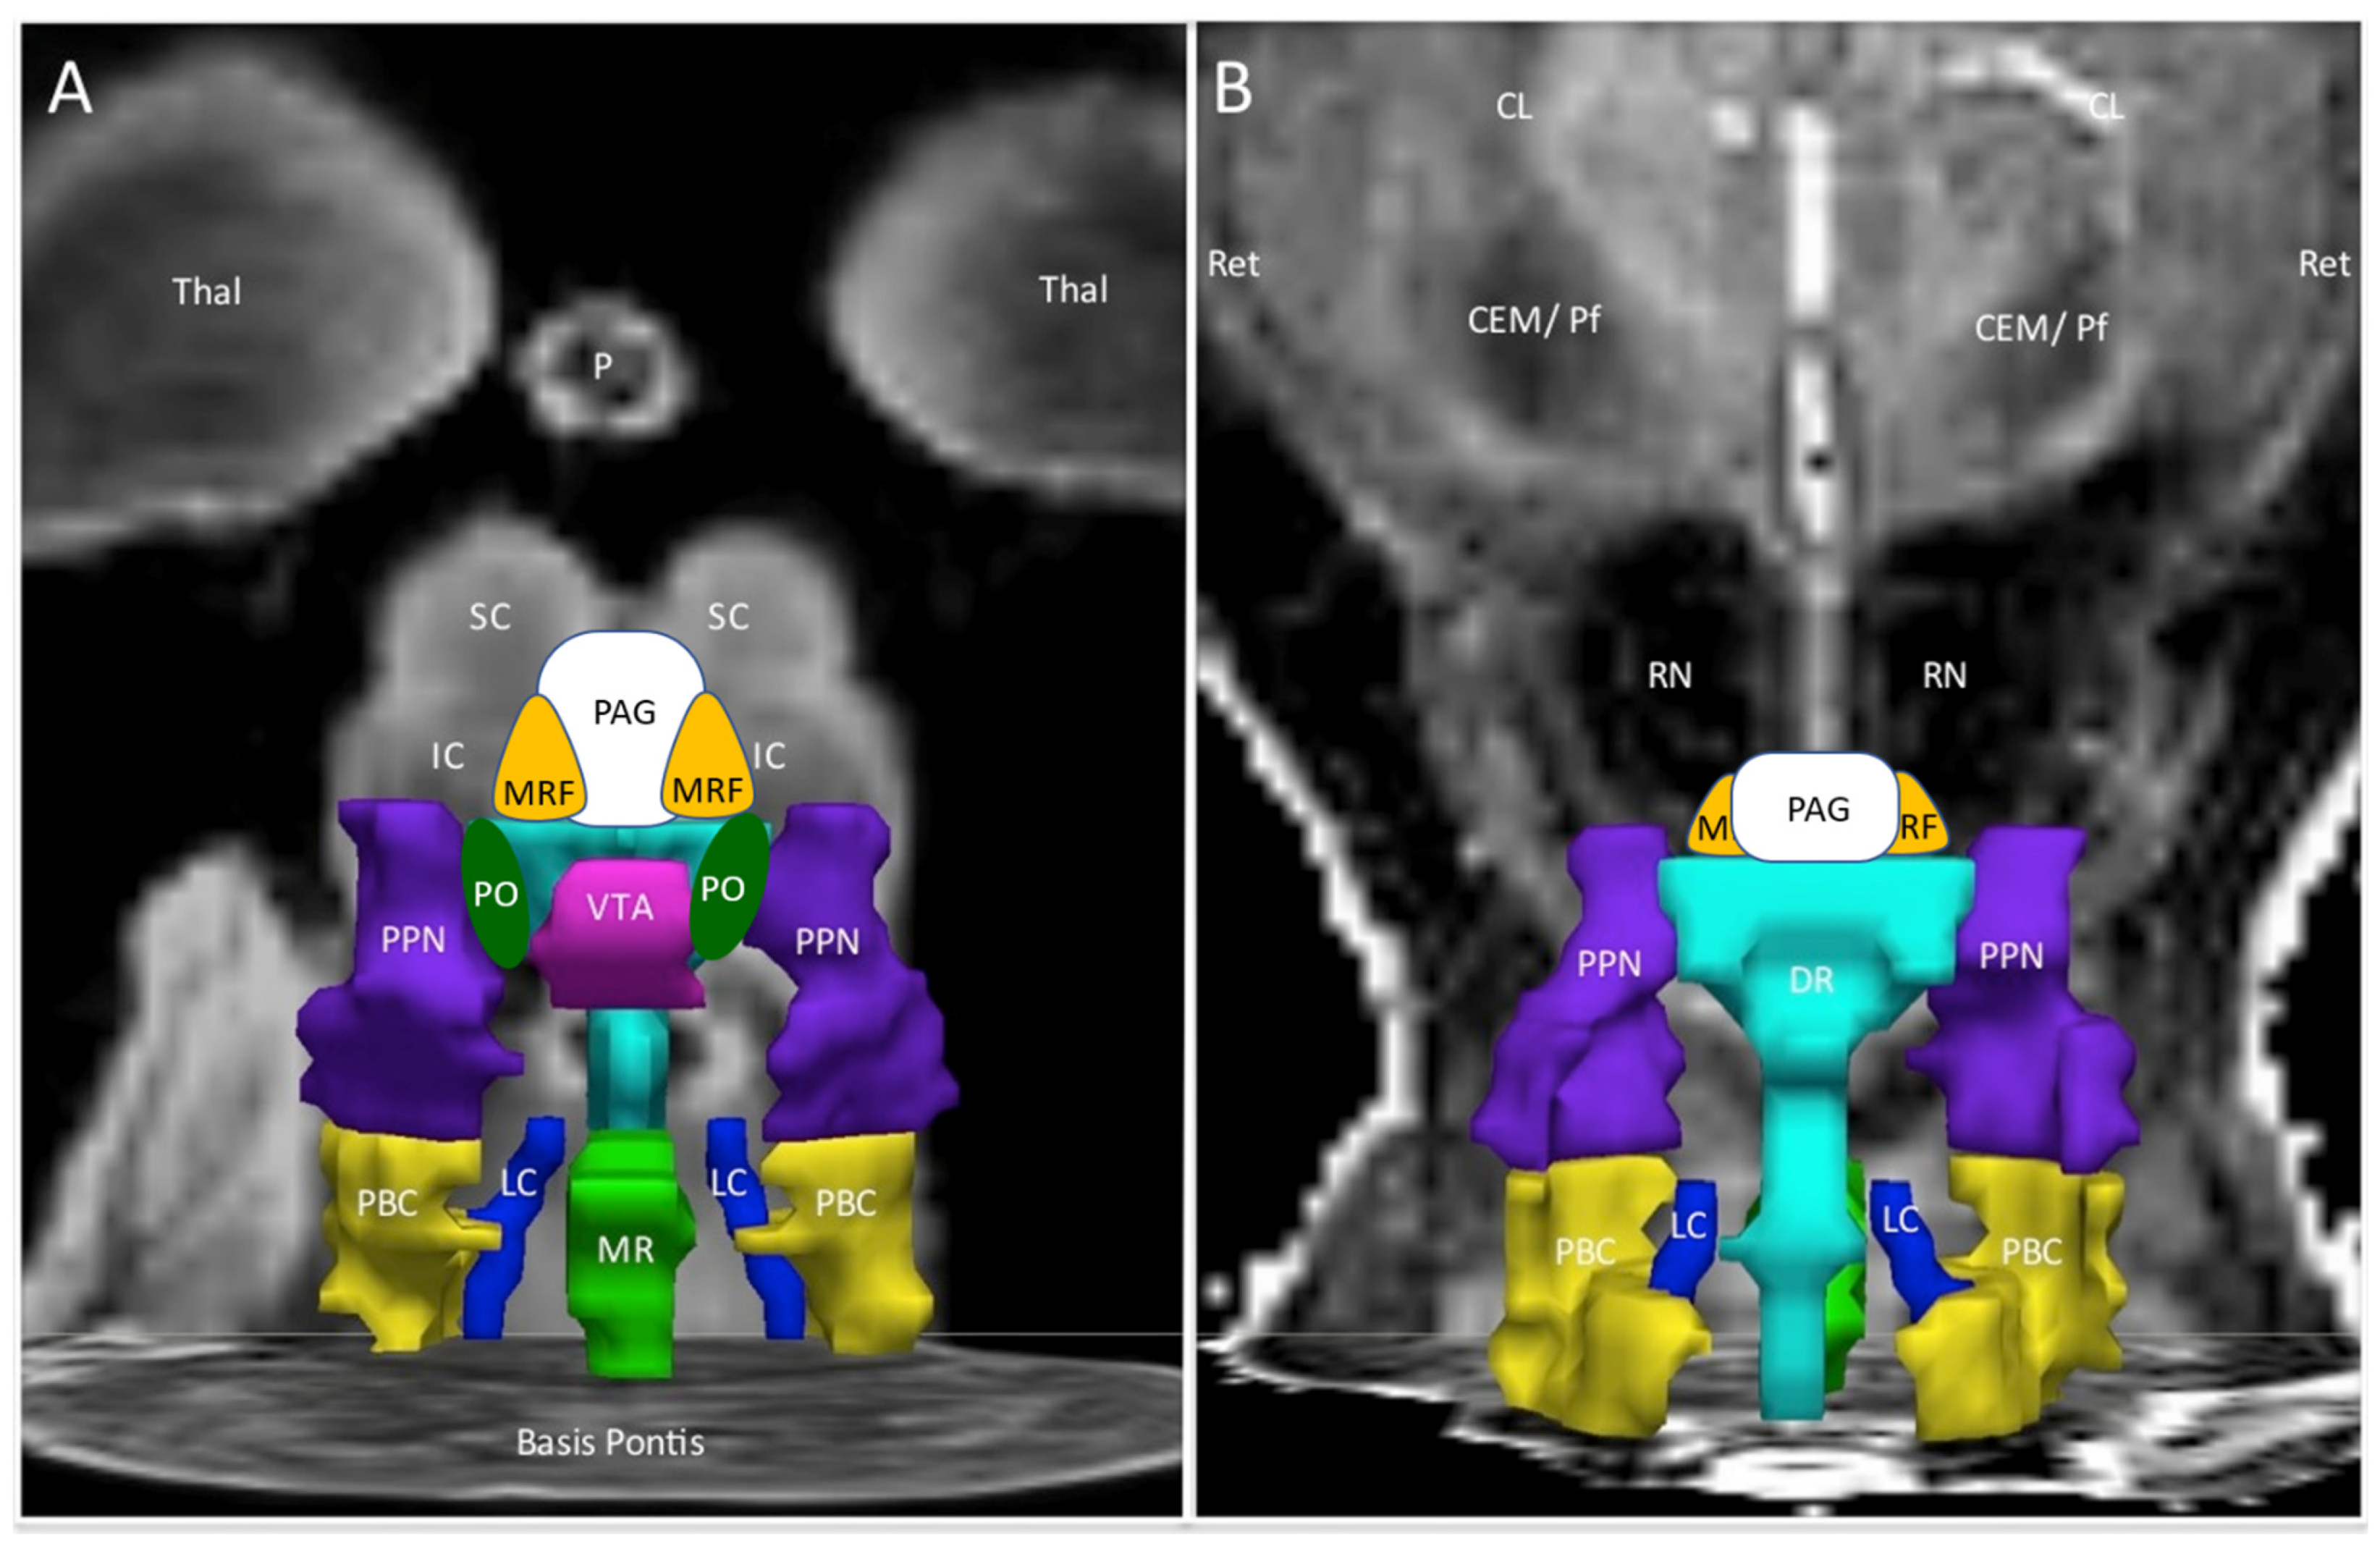

| Abbreviation | Nuclei | Color |

|---|---|---|

| Thal CEM/Pf Ret CL P RN | Background nuclei for orientation thalamus centromedian/parafascicular nucleus reticular nucleus central lateral nucleus of the thalamus pineal midbrain red nuclei Basis Pontis—arbitrary section through the rostral pons to form the “floor” of the figure | grey scale |

| Midbrain and Isthmus (superior to inferior) | ||

| SC | superior colliculus | grey |

| IC | inferior colliculus | grey |

| PAG | periaquequctal grey | white |

| MRF | midbrain reticular formation | orange |

| VTA | ventral tegmental area | violet |

| DR | dorsal raphe | cyan |

| MR | median raphe | lime green |

| PTN | pedunculotegmental nuclei (PTN, formerly PPN pedunculopontine nuclei) | navy blue |

| PO | pontis oralis | dark green |

| PBC | parabrachial complex | yellow |

| LC | locus coeruleus | royal blue |